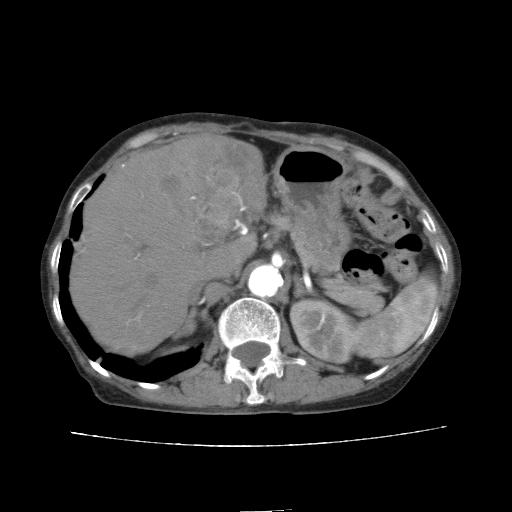

动脉期

看片子胆管里结石,肝上显示的占位会不会是胆管癌?大家帮忙看看,图像不太好,手头的处理文件没有,大致转换了一下,有原始图像数据

1)考虑肝左叶胆管细胞癌并肝内转移。2)肝左叶肝内胆管结石。